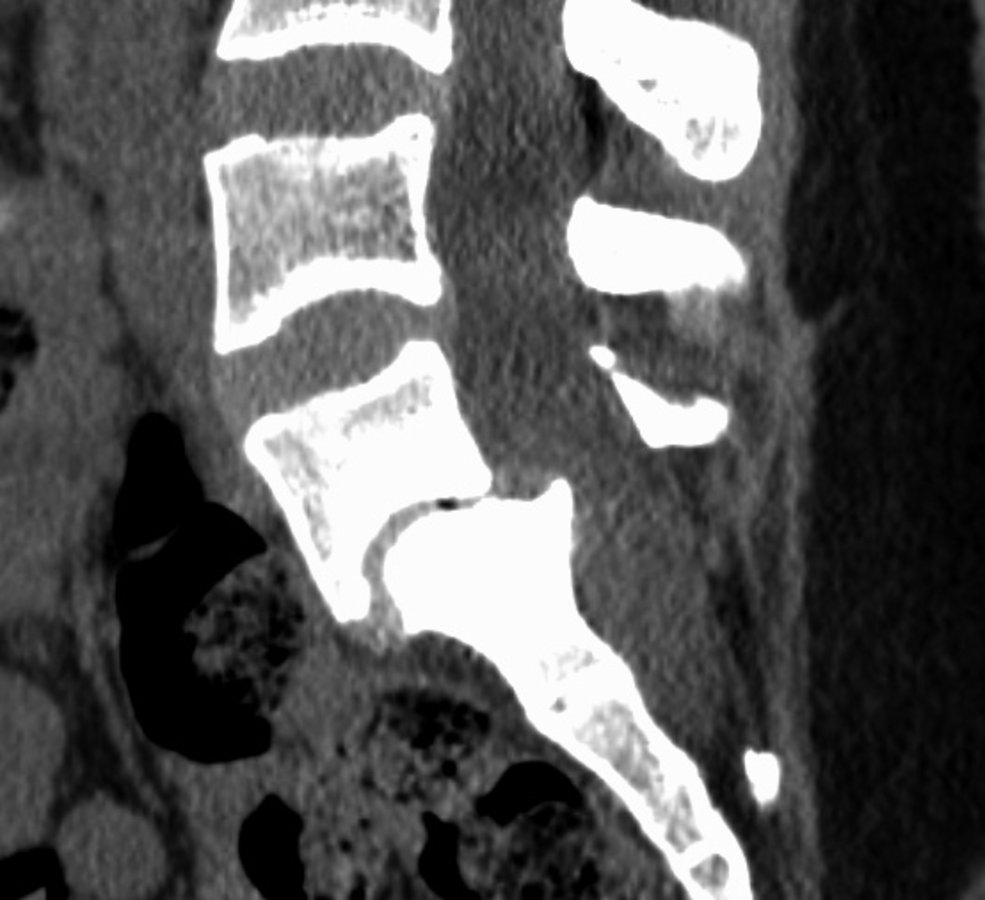

In der Computertomographie zeigt sich eine Spondylolisthesis zwischen L5 und S1. In der Computertomographie zeigt sich eine Spondylolisthesis zwischen L5 und S1. © wikimedia/James Heilman, MD